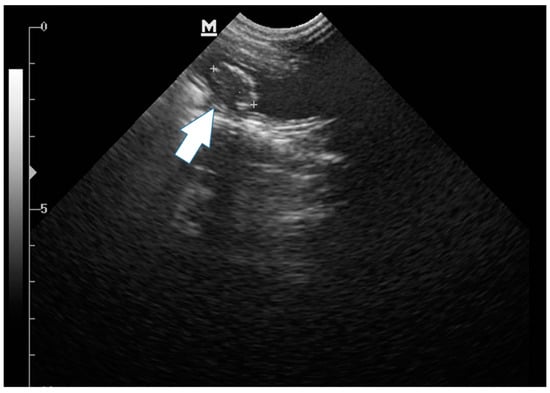

2. Case Description